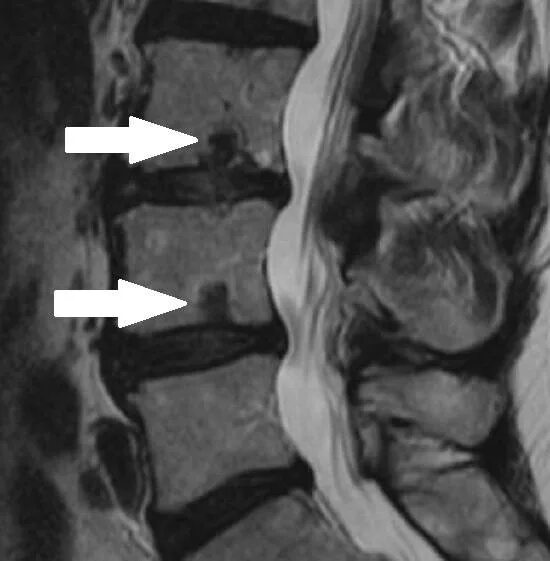

Протрузии шморля